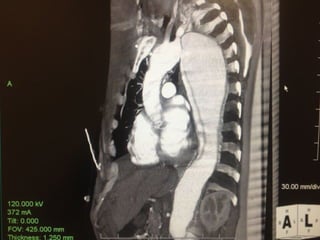

• Preoperative CT 1mm imaging to include pelvisPreoperative CT 1mm imaging to include pelvis